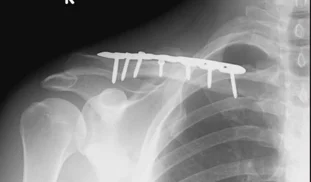

Clavicle Fracture: Management

- Surgical Treatment

- ORIF by Plate and Screws (standard)

- Elastic nail ?